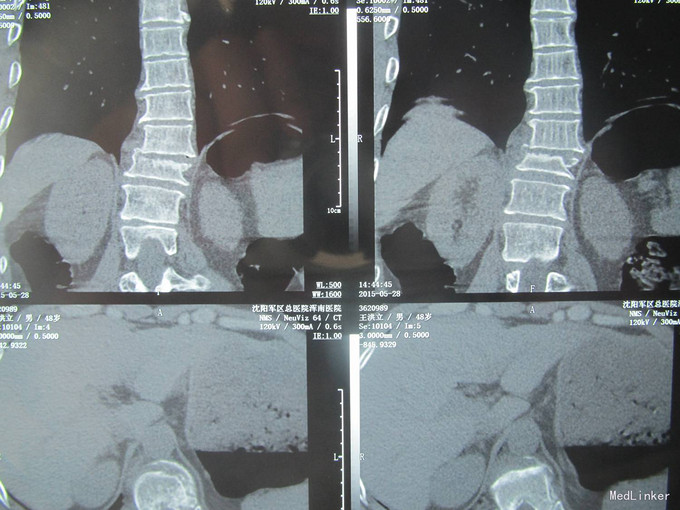

患者及家属述患者于2015-5-28日下午1点,自行驾驶机动车不慎坠入沟中,导致胸腰部疼痛活动受限,无法站立行走。家人急送到沈阳军区总院浑南院区,行CT检查示:胸11椎体压缩骨折;右侧胸11、12腰1横突骨折;胸10、11棘突骨折;右侧肋骨多发骨折;未行任何处理。现患者及家属为求进一步治疗来我院,我科以“胸椎骨折”为主要诊断收入院。患者自受伤以来,无发热,稍感呼吸困难,饮食睡眠正常,二便正常。

入院后完善检查,查无手术禁忌症后行胸11椎体骨折切开复位椎板减压椎弓根钉内固定术